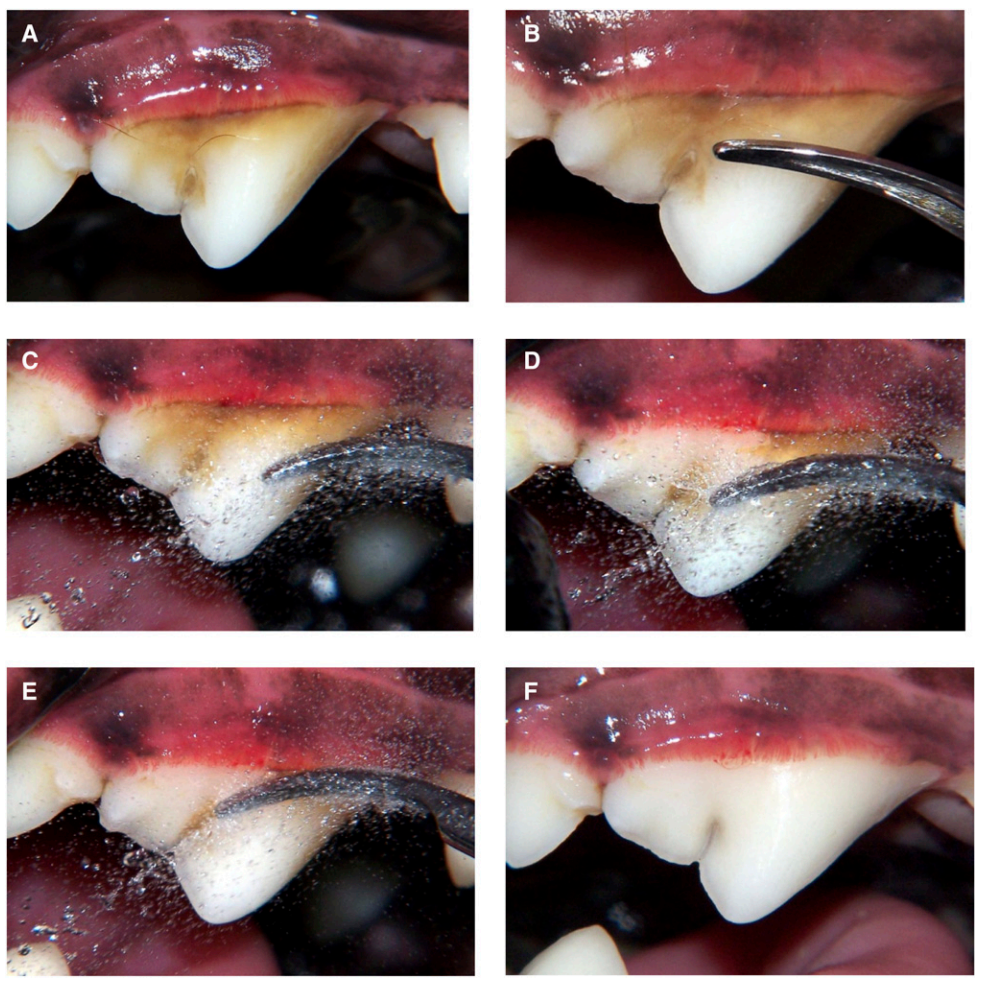

当牙菌斑变成牙结石之后,牙结石是紧贴在牙齿表面的,而为了去除难以清理的牙结石,锋利的刮齿器是洁牙过程中必不可少的的工具。

因此,没有麻醉的话,宠物洁牙会受到很大的限制,兽医或美容师只能清洁眼睛很容易看见且在动物不配合的情况下也可以很容易去除的牙结石。结果就是整个口腔并没有得到真正的清洁,那些在牙龈和牙齿间的看不见的结石和脏东西根本无法被清洁掉。而麻醉让医生得以准确高效地清洁、治疗每一颗牙齿,以及牙龈的每一个角落,达到美观且健康的标准。

麻醉洁牙可以清洁牙龈和牙齿之间的部位 | Tamara Rees